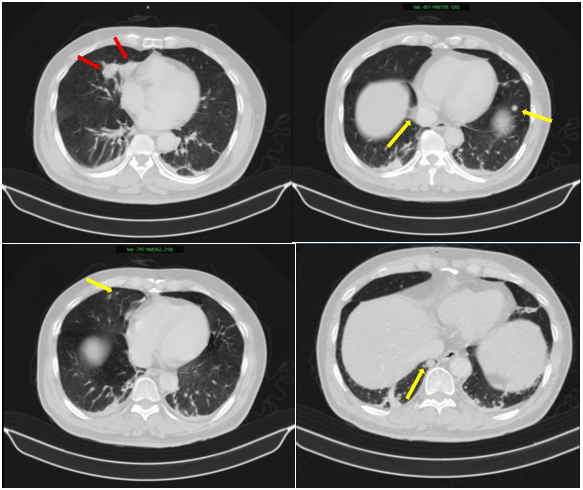

Bệnh nhân được chụp cắt lớp vi tính vùng tiểu khung, phát hiện khối u tại thùy phải của tuyến tiền liệt. Sau đó, bệnh nhân đã được chụp phim cộng hưởng từ nhằm đánh giá chính xác tính chất khối u (Hình 1).

Hình 1:Hình ảnh nốt vùng chuyển tiếp lệch phải (PIRADs 3) trên phim cắt lớp vi tính (mũi tên đỏ) và trên phim cộng hưởng từ (mũi tên vàng).